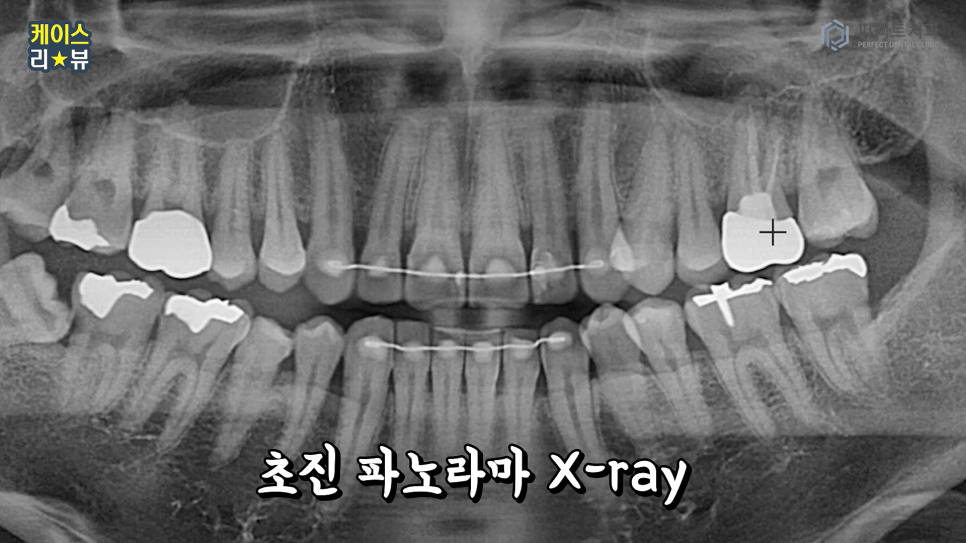

치료 전 상태도 살펴볼 수 있도록 사진을 준비해봤습니다.

사진으로 봤을 때 오른쪽에 신경치료한 치아의 상태가 좋지 못했어요.

고름이 차면서 뼈가 다 녹아버린 경우입니다. 이 부위에 염증이

상악동까지 번져있어 결국 발치를 하게 되었어요.